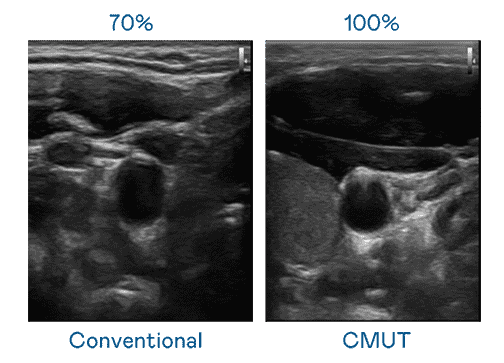

CMUT 技术是一种用电容式微机电元件来产生超音波讯号的技术。。。。与传统 PZT 压电式技术相比,,CMUT 频宽增加 30%,,更宽频的超音波讯号让影像解析度大幅提升,,,是实现高影像品质医疗超音波扫描、、、、促进精准医疗发展的关键技术。。。

大频宽带来超清晰影像

超音波影像的解析度高低,,,首先取决于探头能发出的讯号频宽。。。。龙门国际 CMUT 可提供高清晰的超音波讯号,,,提供高频宽、、、高灵敏度、、、影像纹理细节更高的超音波影像,,,,协助医护人员缩短影像判读时间及利用精准的医疗影像进行诊断。。。